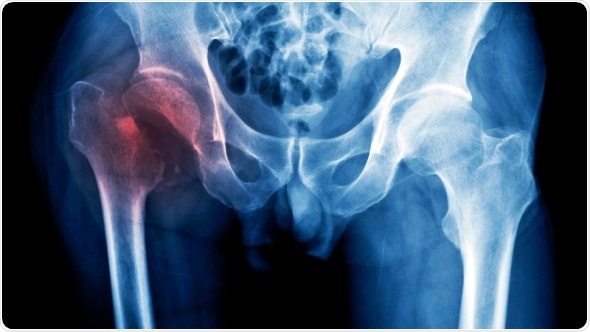

Credit: iStock